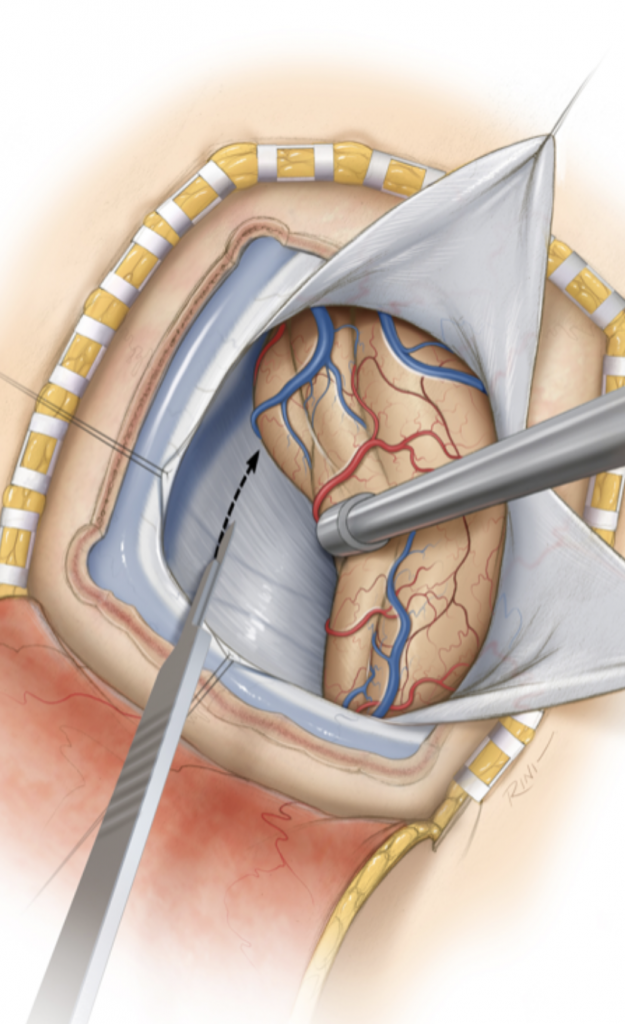

The tumor was causing compression of the upper brainstem and hydrocephalus. The tumor was removed by Dr. Michael Brisman using a right occipital / transtentorial approach.

Figure 2: Images demonstrating the right occipital / transtentorial operative approach.

The traditional surgical approach to this region is the midline supracerebellar approach, performed with the patient in the seated position. We chose instead the right occipital / transtentorial approach. The major advantages of this alternative approach are (1) it is much easier technically for the surgeon, and (2) the risk of a serious air embolus is much lower. The major risk of surgery in the pineal region is injury to one of the large deep veins, which can result in a serious venous infarct.